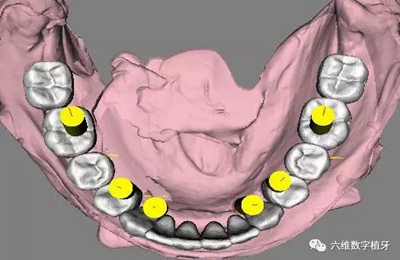

治療計(jì)劃及種植方案設(shè)計(jì)

1. 選擇適當(dāng)?shù)姆N植體尺寸,精確的避開前牙區(qū)骨壁較薄的地方。

2. 預(yù)先在軟件里面進(jìn)行排牙,根據(jù)最終修復(fù)的效果精確放置種植體的位置。

3. 充分評(píng)估患者的骨質(zhì)條件,手術(shù)之前事先將固定的臨時(shí)義齒做好,進(jìn)行即刻負(fù)重。